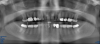

Fig 7. Radiograph showing the patient’s multiple implant restorations.

Figure 7